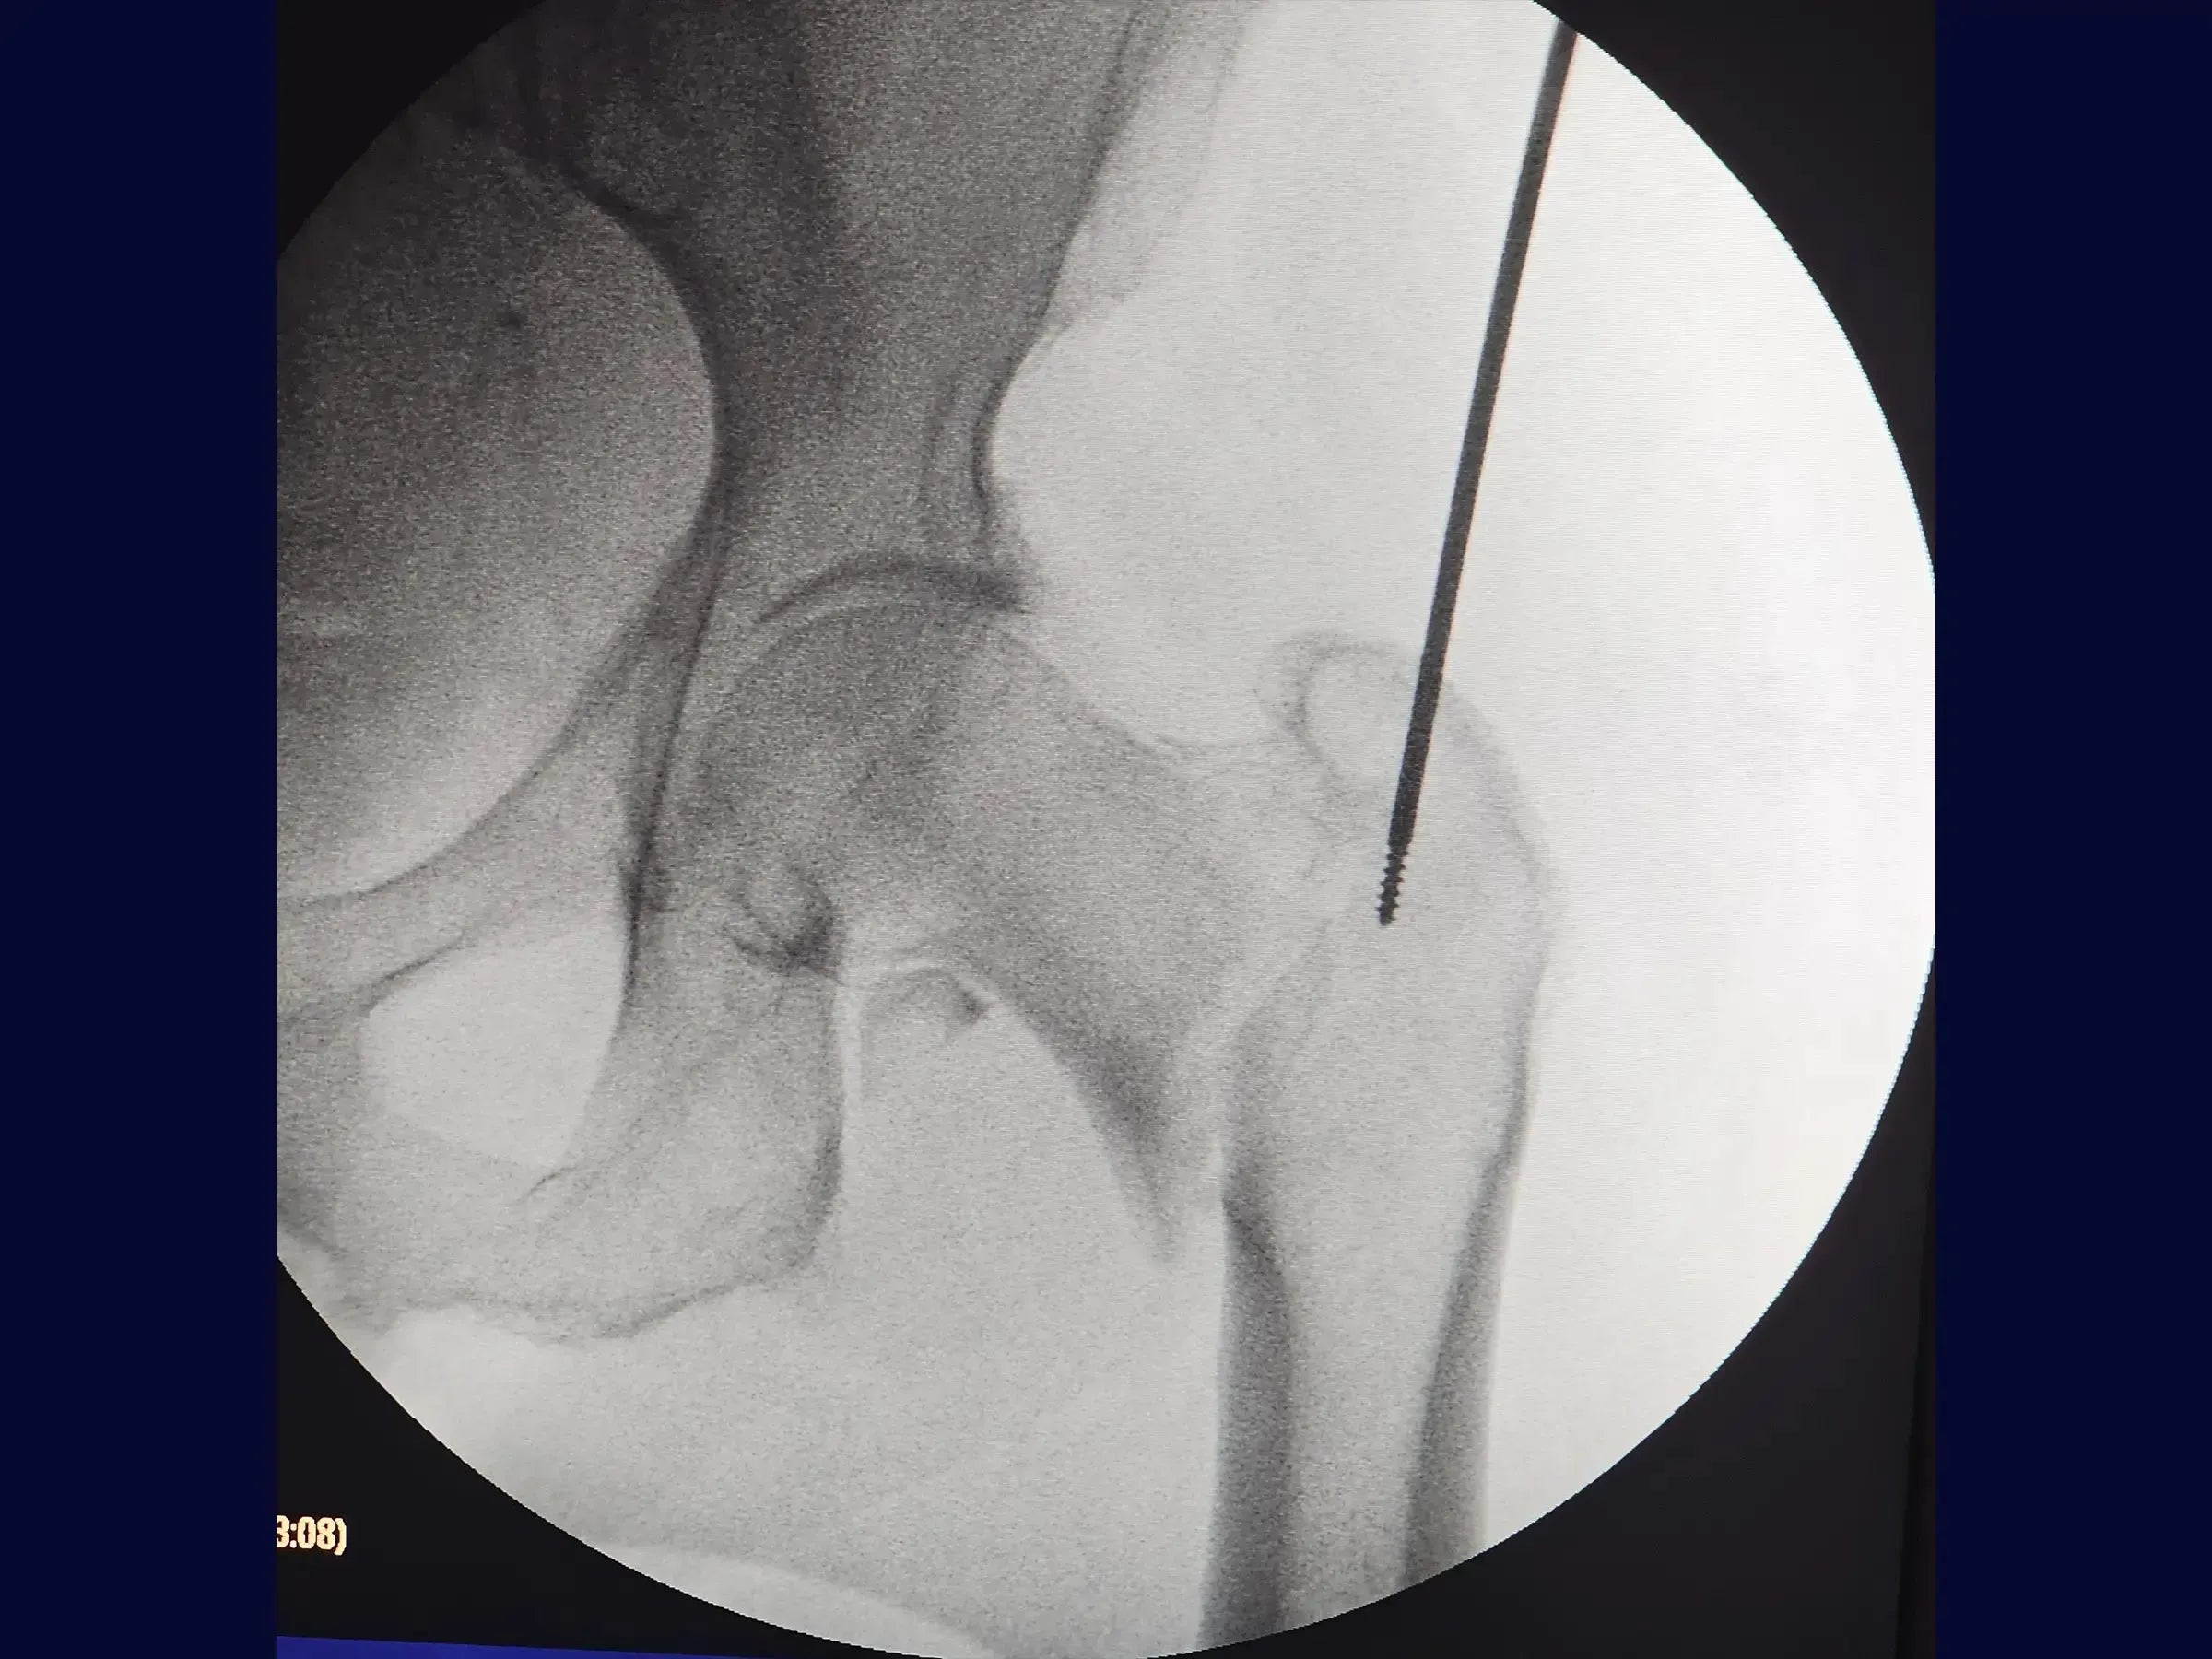

- Manejo de la inserción de guía y apertura del canal medular.

- Inserción precisa de la guía: protocolos para crear el portal de entrada alineado con la espina ilíaca anterosuperior, dar forma a la guía para lograr el mejor ángulo de ataque y realizar una comprobación radiológica para comprobar la centralización y la prevención de la oblicuidad.

- Clavo Intramedular Corto: Abordaje sistemático para la inserción del clavo y la extracción de la guía, considerando los desafíos de la impactación y el desplazamiento en valgo.

- Maniobra de reducción en balancín: Demostración de la técnica de reducción para fragmentos proximales valgos o impactados, incluida la creación de un miniportal seguro y la aplicación de la palanca para obtener y mantener la reducción anatómica con una manipulación mínima.